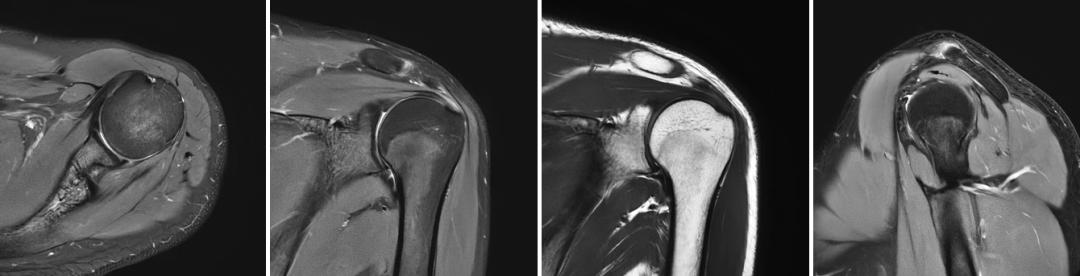

骨关节:膝关节半月板/韧带损伤、肩袖撕裂、股骨头坏死等;

肩关节